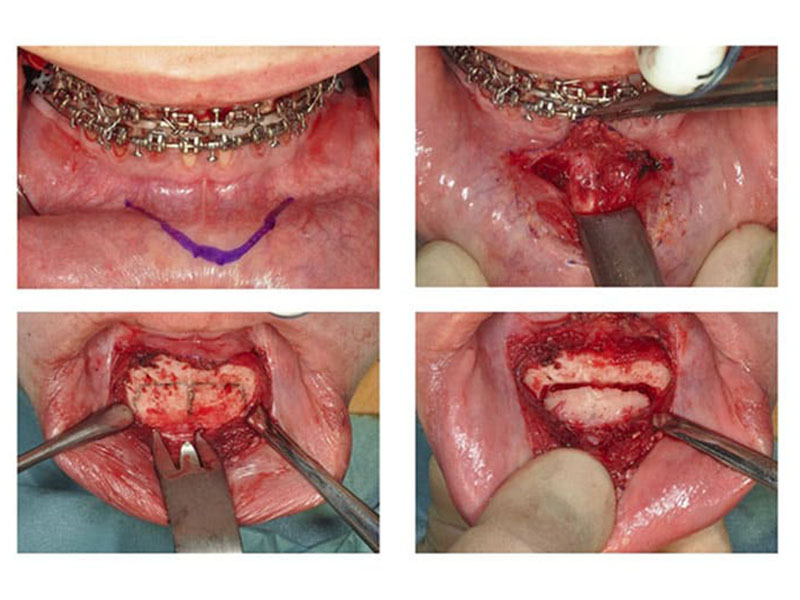

idk u tell me, does it look like it hurts?has anyone had genioplasty?and did it help/hurt after?

You’re acting like you aren’t under anaesthesia lolidk u tell me, does it look like it hurts? View attachment 4316333